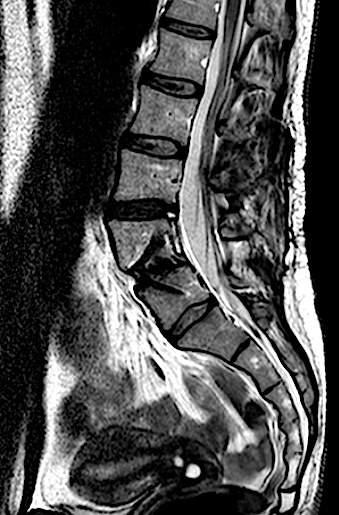

Paciente de 34 años con lumbalgia mecánica refractaria de años de evolución con progresión de la clínica.

En la RM lumbar de control se apreciaba edema en L5-L6 que se interpretó como secundario a sobrecarga mecánica a dicho nivel. Se decidió una fijación percutánea (MIS) L5-L6.

Tras la fijación percutánea, la paciente seguía presentando lumbalgia mecánica (de menor intensidad). Tras agotar opciones de tratamiento conservador, atribuimos como causa la discopatía incipiente L4-L5 (que había progresado).